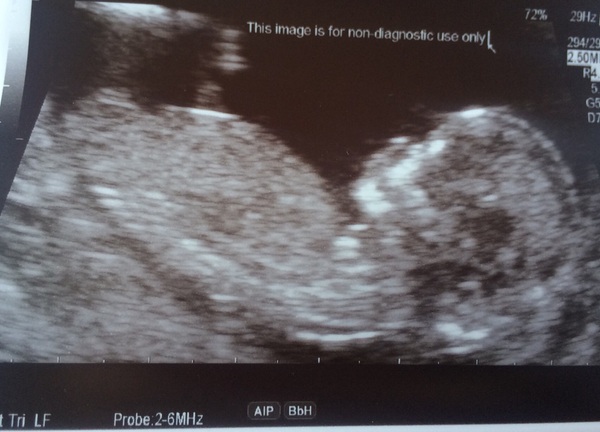

I had my scan today!

It was crazy to see its little arms and legs waving around, and it was swallowing and stretching around.

The sonographer has moved my date forward by a couple of days so I'm 13 weeks today, now due on April 9.